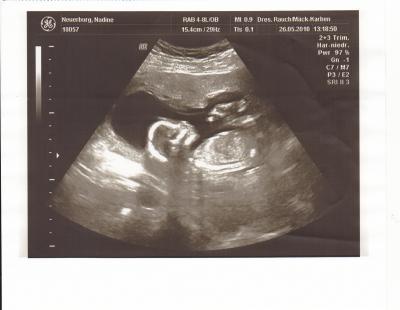

Gestern hatte ich wieder VU und es ist alles bestens mit unsrem Krümel-wächst und gedeiht prächtig-alles so wie es sein soll. Jetzt hab ich auch endlich mal ein wenig zugenommen- 1Kilo mehr hab ich jetzt seit Beginn der SS. Und vom Babybauch is zwar auch noch nich wirklich viel zu sehen, aber dafür war gestern im Ultraschall jemand extrem zeigefreudig.....WIR KRIEGEN MIT HÖCHSTER WAHRSCHEINLICHKEIT EINEN JUNGEN!:-) Ich freu mich so,denn ein Geschwisterpäarchen wollte ich immer gerne haben und meine Tochter rennt ohnehin nur rum und sagt: "Ich will einen Bruder, Mama"..und mein Freund is happy,weil die Frauen dann endlich nich mehr in der Überzahl sind daheim:-) Anyway-ICH BIN MEGAGLÜCKLICH DAS ALLES IN ORDNUNG IS...und falls das mit dem Geschlecht eine Fehleinschätzung gewesen sein sollte, nehmen wir natürlich auch gern ein Mädchen:-) Hier auch noch das Ultraschallbild von gestern.

Bild zu Gestern VU & Outing - Forum für November - Mamis